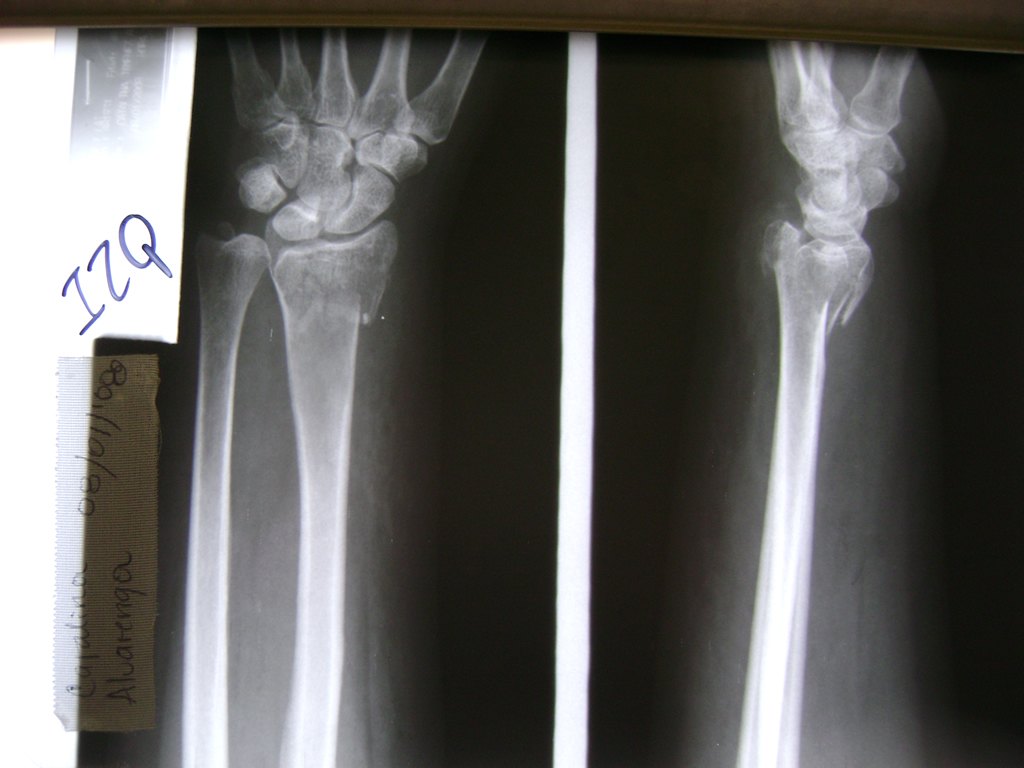

Cirugías de Húmero - Cirugías de Muñecas y Manos

Los procedimientos más comunes en cirugía de la mano son aquellos destinados a reparar traumatismos, incluyendo lesiones de tendones, nervios, vasos sanguíneos, y articulaciones; huesos fracturados; y quemaduras, cortes, y otros daños de la piel.